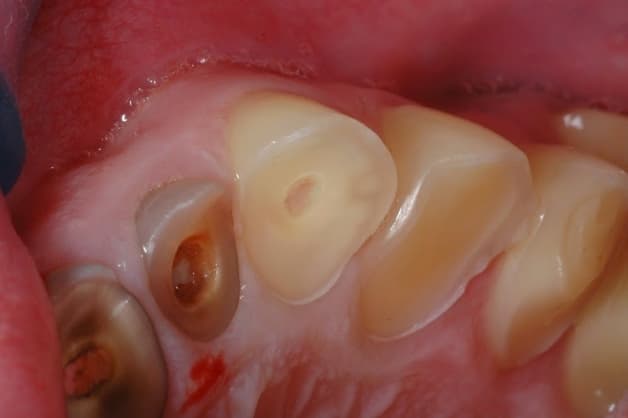

Tình trạng mòn mặt răng có 3 mức độ

Răng bị mòn mặt nhai là tình trạng bề mặt của răng bị tổn thương do mất mô răng. Khi men răng bị mất đi, cấu trúc của răng cũng sẽ có những thay đổi. Các vết lõm nông hoặc vết sâu trên bề mặt răng sẽ xuất hiện.

Tình tràn mòn mặt nhai diễn ra có 3 mức độ khác nhau:

– Mức độ nhẹ: Tình trạng mòn mặt nhai xảy ra ở lớp men răng.

– Mức độ nghiêm trọng hơn: Sự ảnh hưởng không chỉ dừng lại ở lớp men răng. Phần ngà răng cũng dần bị phá hủy kèm theo tình trạng răng ê buốt, đau nhức răng.

– Mức độ nguy hiểm nhất: Ở giai đoạn này, răng đã yếu và xuất hiện tình trạng đổi màu, lung lay. Đến một mức độ nhất định, tủy răng của người bệnh cũng sẽ bị ảnh hưởng.